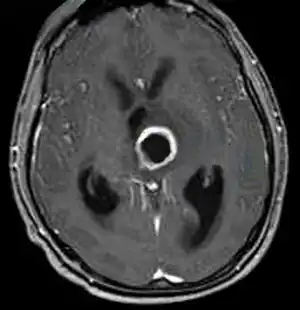

Clinically it is associated with abscess formation in the upper body and respiratory tract. It has also been found to be involved with pulmonary exacerbations in cystic fibrosis patients and can lead to toxic shock and limb amputation.[7]